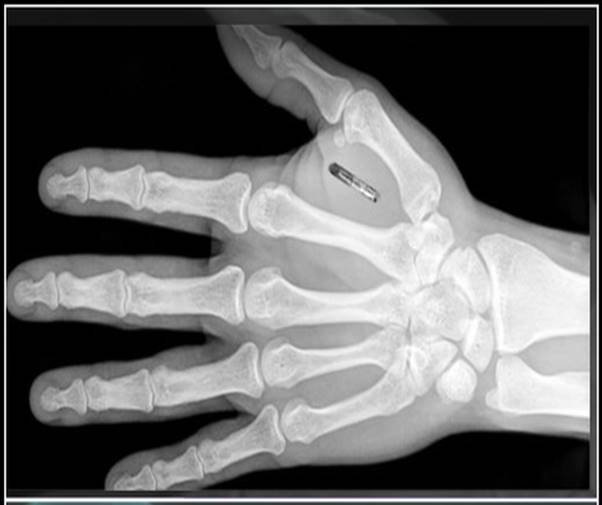

Elektroniczne identyfikatory, nazywane popularnie "czipami" (spolszczona wersja angielskiego terminu "chip", używanego praktycznie na całym świecie do nazywania dowolnego mikroukładu elektronicznego) są od dawna stosowane do trwałego oznaczania zwierząt.

Ale ostatnio pojawiły się pomysły, żeby takie czipy identyfikacyjne wszczepiać także ludziom. Zwolennicy tej techniki wskazują, że człowiek mający w swoim ciele czip będzie mógł go używać zamiast identyfikatora umożliwiającego wstęp do określonych pomieszczeń, dostęp do określonych zasobów, wybieranie pieniędzy w bankomacie czy płacenie rachunków w sklepie i w restauracji. Ja jednak jestem przeciwny takiemu wszczepianiu do ciała człowieka urządzenia, które będzie go stale i wszędzie identyfikować, odbierze mu resztkę prywatności (i tak ciągle jesteśmy na dziesiątki sposobów monitorowani, podglądani i podsłuchiwani!). Ponadto rozwój takich personalnych czipów doprowadziłby z czasem nawet do ataków hakerów na nasze ciało!